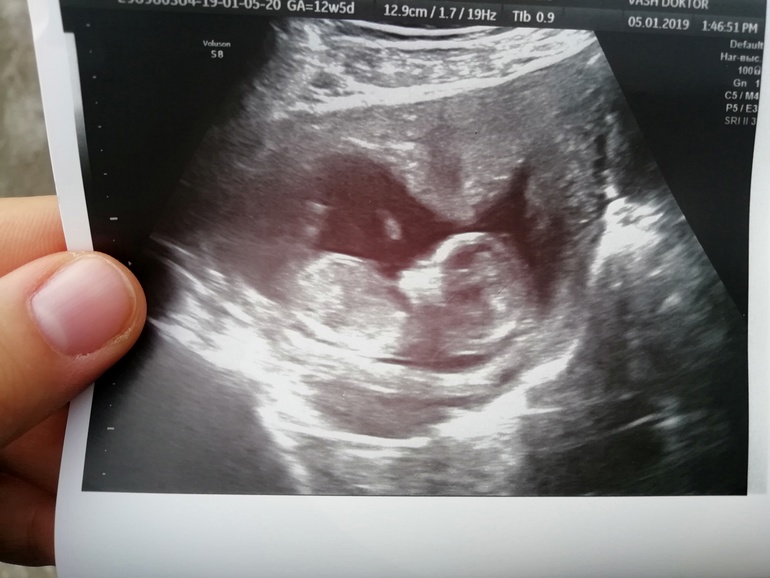

Добрый день 😍вышла с узи, и хочется летать, пархать, кричать и все от радости 🙈когда начали показывать эти ручки, ножки, животик, головку, я тюфяк, давай слезы подбирать... Спросила кто, сказали похоже на девочку.. Когда-то ниже писала, что хочу пацана, так вот сегодня после УЗИ поняла, что абсолютно все равно, я безумно рада и девочке и мальчику... Она просто чудесная, во время узи мы сладко спали сложив ручки на животике 🙈😍❤️меня распирает от счастья и любви к ней 😭😍 Узистке очень пришлось постараться поймать, матка была в тонусе, как она пояснила то ли это вы мамочка так перенервничали то ли это джинсы узкие, которые посоветовала сменить, но с джинсами конечно я сегодня вообще надурила, все из-за своей рассеяности.. А так сказали все у нас хорошо, до 9 январь кровь сдайте)